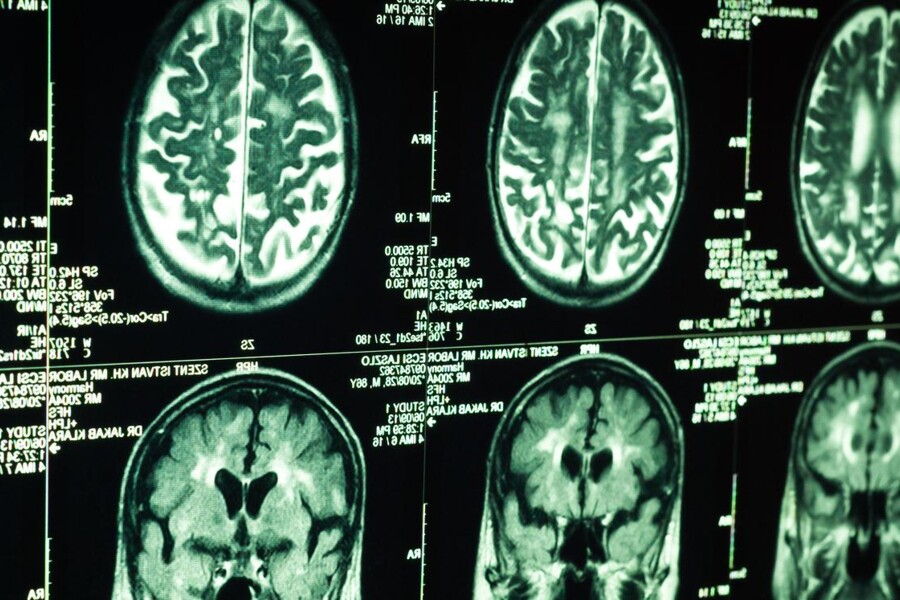

Během pravidelných prohlídek lékař měří dítěti obvod hlavy a porovnává ho tabulkami udávajícími normální hodnoty pro příslušný věk dítěte. Abnormálně velká hlava nebo rychle se zvětšující hlava upozorní lékaře na možnost hydrocefalu. Lékař vyšetří dítěti hlavu počítačovou tomografií, magnetickou resonancí nebo ultrazvukem a na základě výsledků vyšetření stanoví diagnózu a určí příčinu.